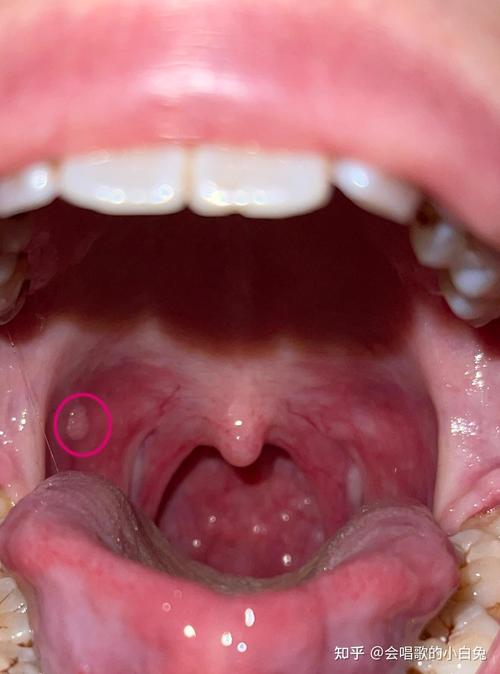

粘液腺囊肿

- 特点:通常是半透明、柔软或略带韧性的小包,像一颗“水珠”,常见于下唇内侧,但也可能出现在下颚内侧,通常不痛,但有时会因咬到而变大、变硬甚至疼痛。

- 成因:由于唾液腺导管被堵塞,唾液无法正常排出,积聚形成囊肿。